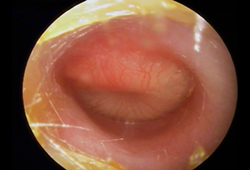

On otoscopy there is erythema and injection of the tympanic membrane in the neutral position without other features of otitis media.[63]

[Figure caption and citation for the preceding image starts]: Otoscopy of myringitis, showing erythema and injection of the tympanic membrane in the neutral positionFrom the personal collection of Dr Armengol [Citation ends].